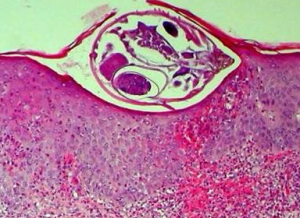

疥瘡患者在陰部特別是男性的陰囊可見黃豆大小的結節,質地較硬,瘙癢劇烈,這種結節是由於人體局部對疥蟲的一種反應所致。嚴格來說,疥瘡結節是由於人體對疥蟲的一種過敏反應,組織病理顯示疥瘡結節主要以嗜酸性白細胞

免疫螢光研究提示在皮膚血管中有血管炎樣改變並出現IgM和C3補體結合物說明疥瘡有體液免疫成分組織學則提示一般疥瘡的皮損中細胞免疫反應引發例如皮損丘疹結節等周圍的浸潤細胞大多數為淋巴細胞而且主要是T淋巴細胞 。